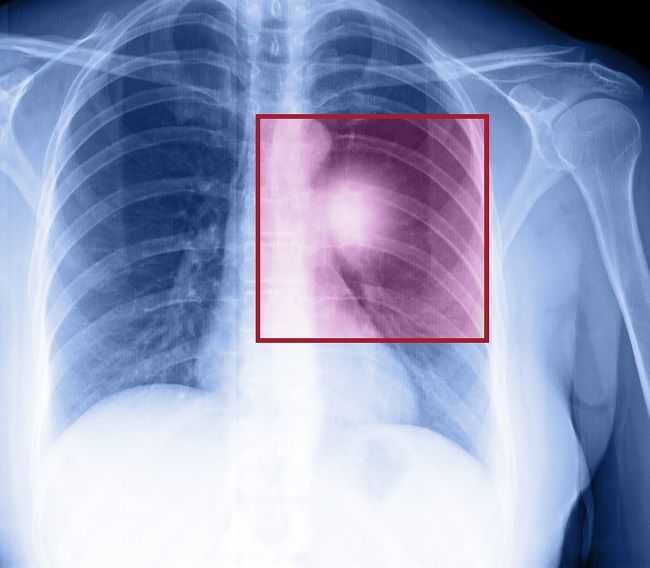

Tumor paru jinak umumnya tidak bergejala. Akibatnya, tumor paru terkadang baru diketahui ketika penderita menjalani foto Rontgen dada untuk pemeriksaan kondisi lain. Namun, tumor jinak dapat menyebabkan gejala jika ukurannya sudah besar dan menyumbat saluran pernapasan.

Diagnosis tumor paru dilakukan dengan menanyakan gejala, riwayat kesehatan pasien dan keluarga, serta gaya hidup pasien. Setelah itu, dokter akan melakukan pemeriksaan fisik, terutama pada dada.

Untuk menetapkan diagnosis, dokter akan melakukan pemeriksaan lanjutan di bawah ini:

Pemeriksaan di atas dapat membedakan tumor yang jinak atau ganas. Dari foto, tumor yang jinak biasanya berukuran kecil, memiliki bentuk dengan batas yang halus pada hasil foto, dan tidak berkembang dengan cepat ketika dilakukan pemeriksaan lanjutan.